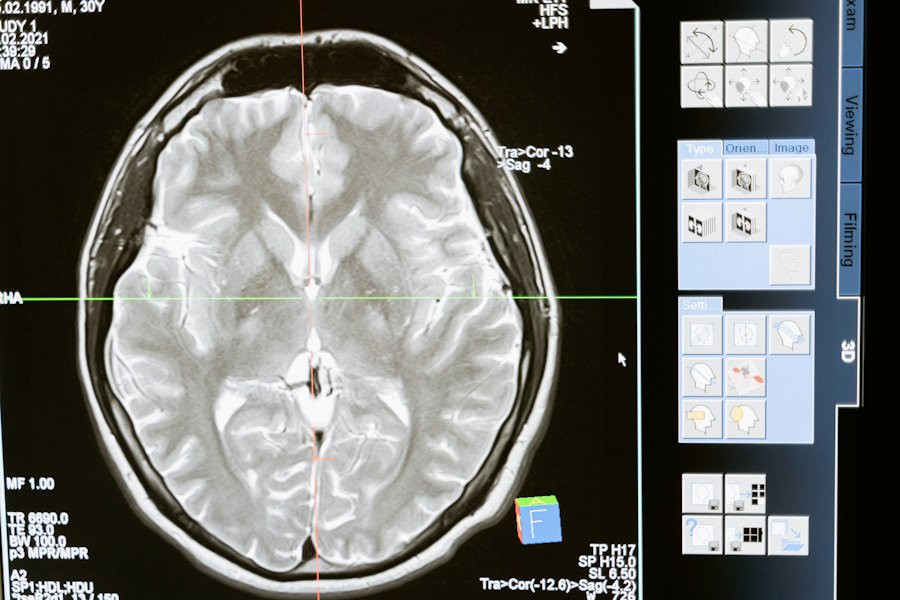

Эпидемия ожирения становится всё более проблематичной в современном обществе, и исследователи признают, что понимание механизмов, лежащих в основе пищевого поведения, является критически важным. Ученые сосредоточились на нейронах дорсального вагусного комплекса (DVC) ствола мозга, которые получают информацию от пищеварительной системы и регулируют потребление пищи.

В ходе исследования было обнаружено, что определенные нейроны, экспрессирующие γ-аминомасляную кислоту в DVC (GABA DVC), играют важную роль в контроле аппетита и массы тела. С использованием метода одноядерного секвенирования РНК (Nuc-seq) ученые выявили 19 отдельных кластеров экспрессии генов в клетках GABA DVC. Далее они провели исследование функции этих клеток и обнаружили, что активация нейронов GABA DVC существенно влияет на потребление пищи.